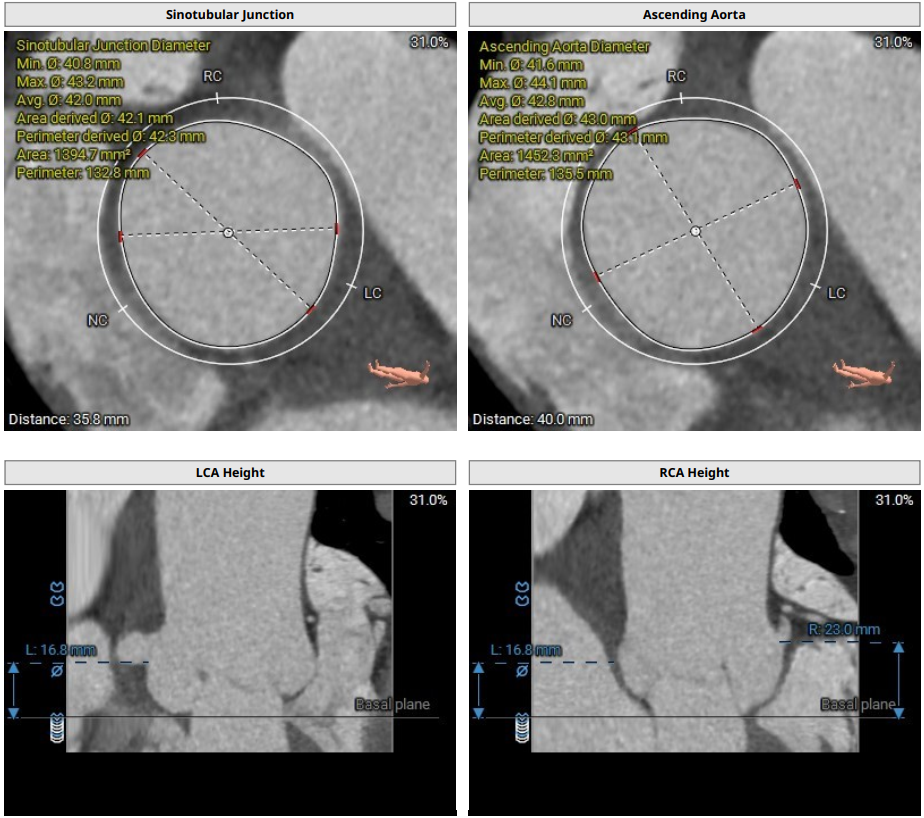

CT评估:三叶式主动脉瓣,无钙化,瓣环27.9mm,窦直径44-46mm。

主动脉根部解剖